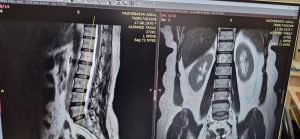

Сменить фото Вашей обложкиЗагрузить Сменить фото Вашей обложкиЗагрузить admin Статус этой учётной записи - Принято О себе О себе Записи Записи Комментарии Комментарии В конце 2025 года в ГМБ и КДЦ были приобретены современные аппараты для оснащения реабилитационного отделения 1 неделя назад в Новости нет комментариев 2 месяца назад в Новости нет комментариев Благодарственные письма от пациентов 3 месяца назад в Новости нет комментариев О совершенствовании профессиональной компетенции лабораторных специалистов Жамбылской области 3 месяца назад в Новости нет комментариев Гемангиома позвоночника 3 месяца назад в Новости нет комментариев Профилактика ОРВИ, гриппа 3 месяца назад в Новости нет комментариев Визит профессора Ш.Ш.Жураева 4 месяца назад в Новости нет комментариев #MedSafetyWeek – бұл дәрілік заттардың жағымсыз әсерлері туралы хабардарлықты арттыруға бағытталған жаһандық ақпараттық науқан. 4 месяца назад в Новости нет комментариев Управление здравоохранения акимата Жамбылской области провело 27-28 августа текущего года на базе Городской многопрофильной больницы и консультативно-диагностического центра вебинар-лекцию на тему «Основные аспекты развития трансплантологии». 4 месяца назад в Новости нет комментариев 11-қазан күні “QazMed” кәсіподағы Жамбыл облысы филиалының ұйымдастыруымен медициналық ұйымдар арасында облыстық спартакиада өтті 4 месяца назад в Новости нет комментариев загрузить ещё записи